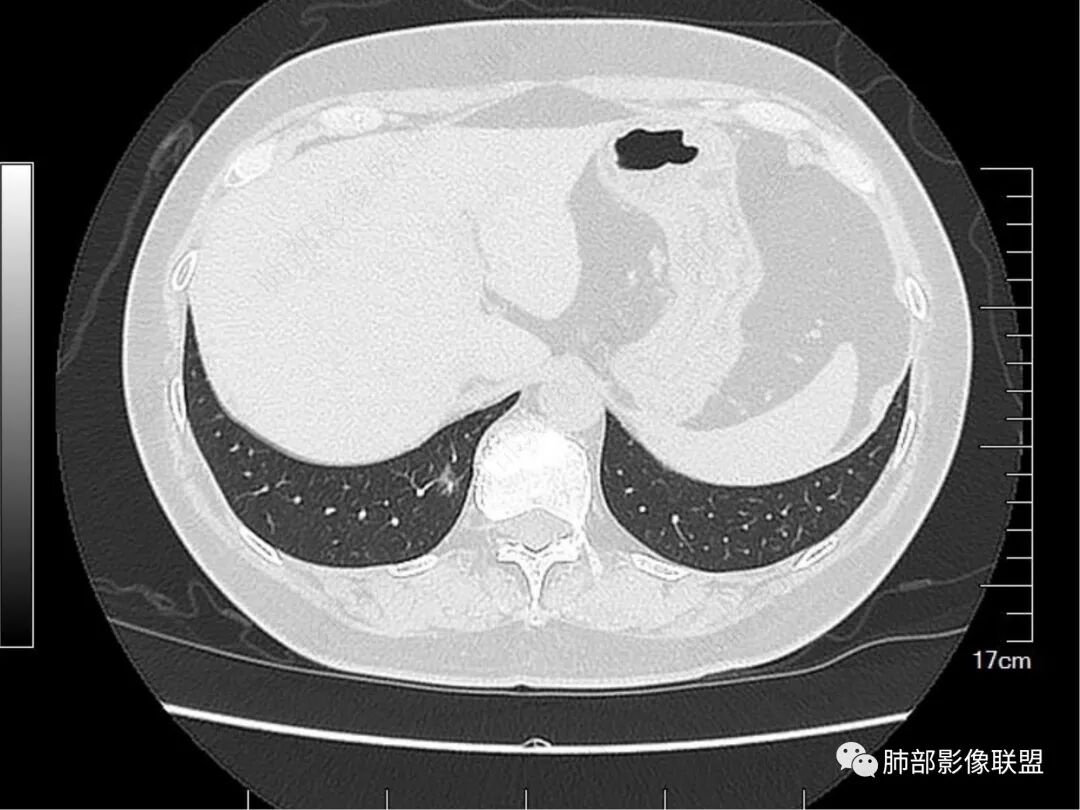

请仔细观察病灶周围情况,比如临近血管、临近胸膜。有个特点,胸膜牵拉并不明显,邻近血管走行还算正常。

这里,可以佐证了。假如支气管扩张是收缩力引起的,而且支气管扩张如此明显,它周围的组织不会一丁点表现没有,离胸膜如此的近,竟然一点牵拉的意思都没有。